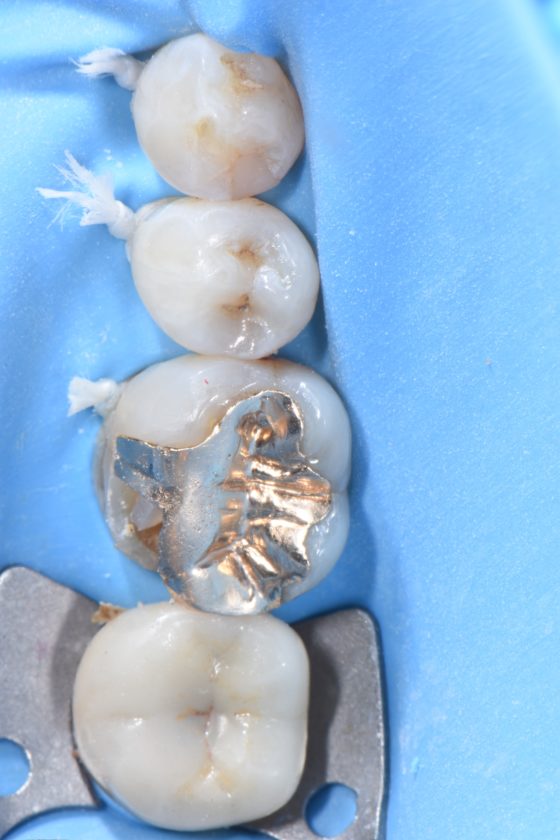

宇部市歯医者ブログ ラバーダム防湿とダイレクトボンディング 白い歯 ...